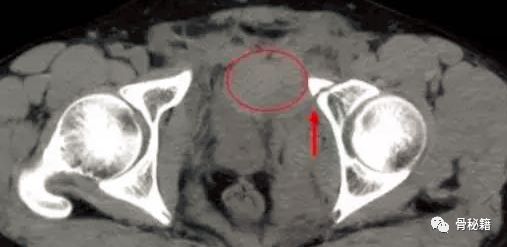

1.受伤时怀疑损伤可以做CT,腹部B超,腹腔穿刺等来进行诊断,B超的敏感性不强,CT有时可以发现耻骨附近的血肿。实在不行可以做造影。

行CT,发现腹腔有10*10*15的血肿位于耻骨骨折旁边。

行血管造影后确定了为死亡之冠出血,后行血管栓塞闭孔动脉后,出血停止。一周后康复出院。